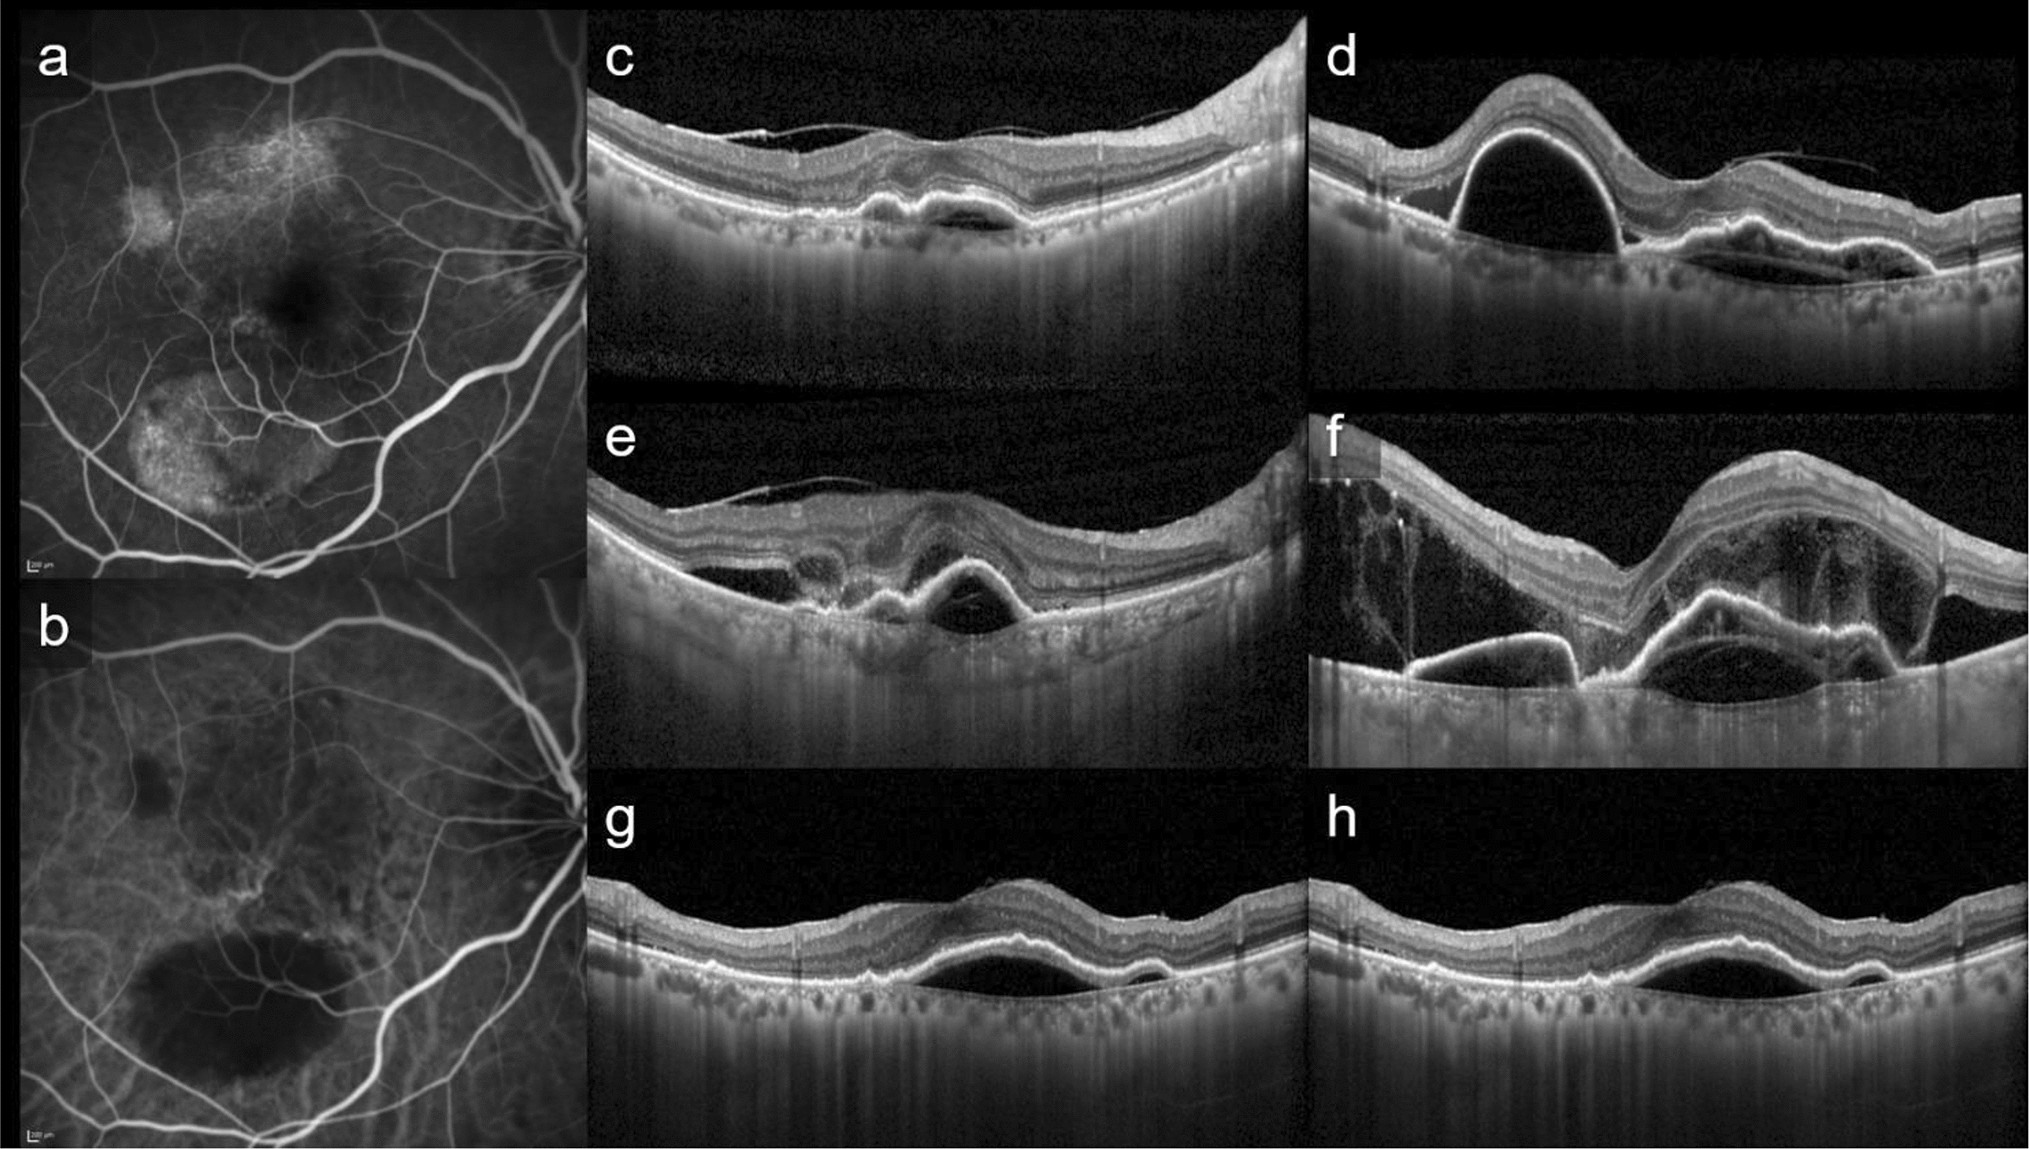

Figure 2

This is a representative case of PAEM+. Fluorescein angiography (a), indocyanine green angiography (b), and horizontal (c, e, g) and vertical (d, f, h) line of optic coherence tomography images of patients at baseline (c, d), 3 days follow-up (e, f) and 1 month follow-up (g, h) after photodynamic therapy (PDT). 82-year-old-female with polypoidal choroidal vasculopathy in the light eye. Central retinal thickness was 361 µm at baseline, 538 µm (+ 49.0%) at 3 days, 334 µm (− 7.5%) at 1 month after PDT. Central choroidal thickness was 135 µm at baseline, 270 µm (+ 100.0%) at 3 days, 126 µm (− 6.7%) at 1 month after PDT. The subretinal fluid increased at 3 days follow-up, with complete resolution at 1 month follow-up. The bacillary detachment was also seen only at 3 days follow-up.